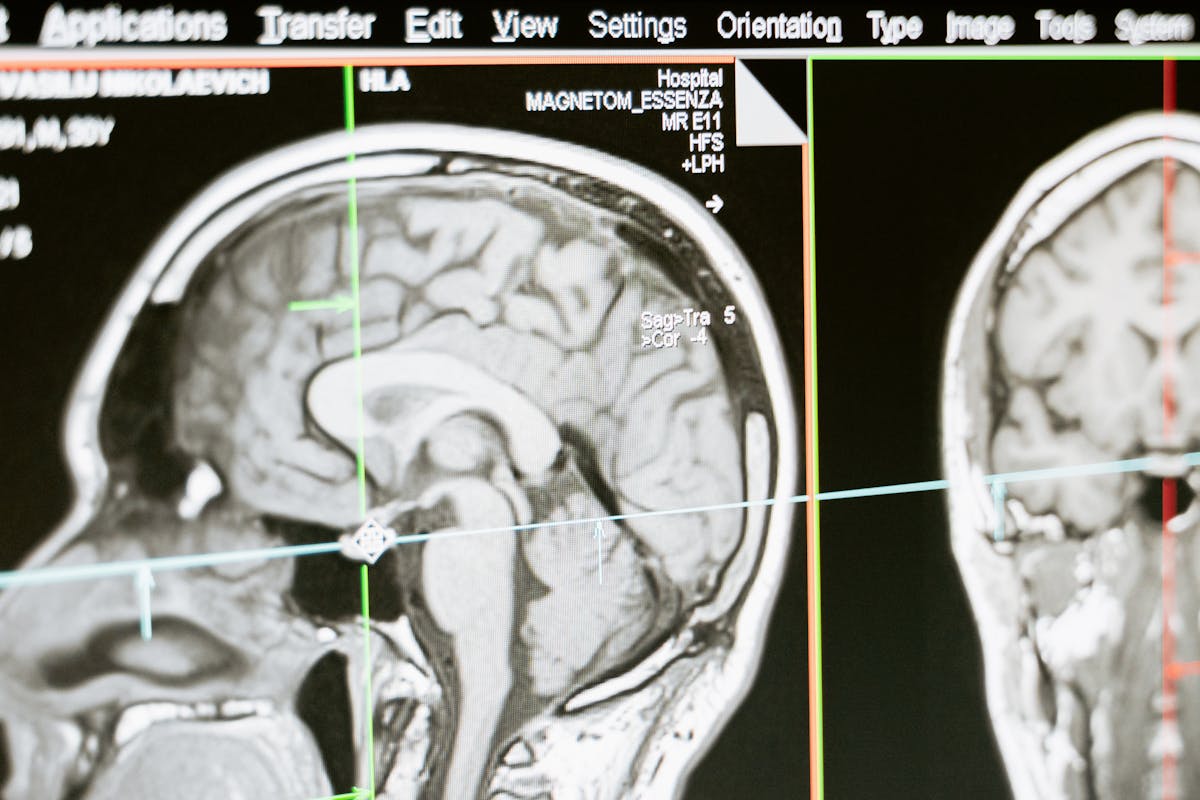

Santé · Images médicales

Diagnostic assisté par IA pour un réseau de cliniques.

Un réseau de cliniques françaises souhaitait accélérer le tri de dossiers d’imagerie (IRM, scanner) afin de prioriser les cas urgents sans surcharger les équipes médicales.

Mise en place d’un pipeline d’analyse d’images basé sur des réseaux neuronaux convolutionnels, entraînés sur des données anonymisées, avec un module d’explicabilité (heatmaps) pour aider les radiologues à interpréter les résultats.

Interface de diagnostic assisté par IA

Schéma simplifié du pipeline :

1. Import DICOM depuis le PACS.

2. Anonymisation & vérifications qualité.

3. Passage dans le modèle CNN (GPU).

4. Calcul de scores de priorisation & génération de heatmaps.

5. Restitution dans le viewer interne + validation par le radiologue.

Tous les événements sont tracés (logs, version du modèle, seuils utilisés) pour audit ultérieur.